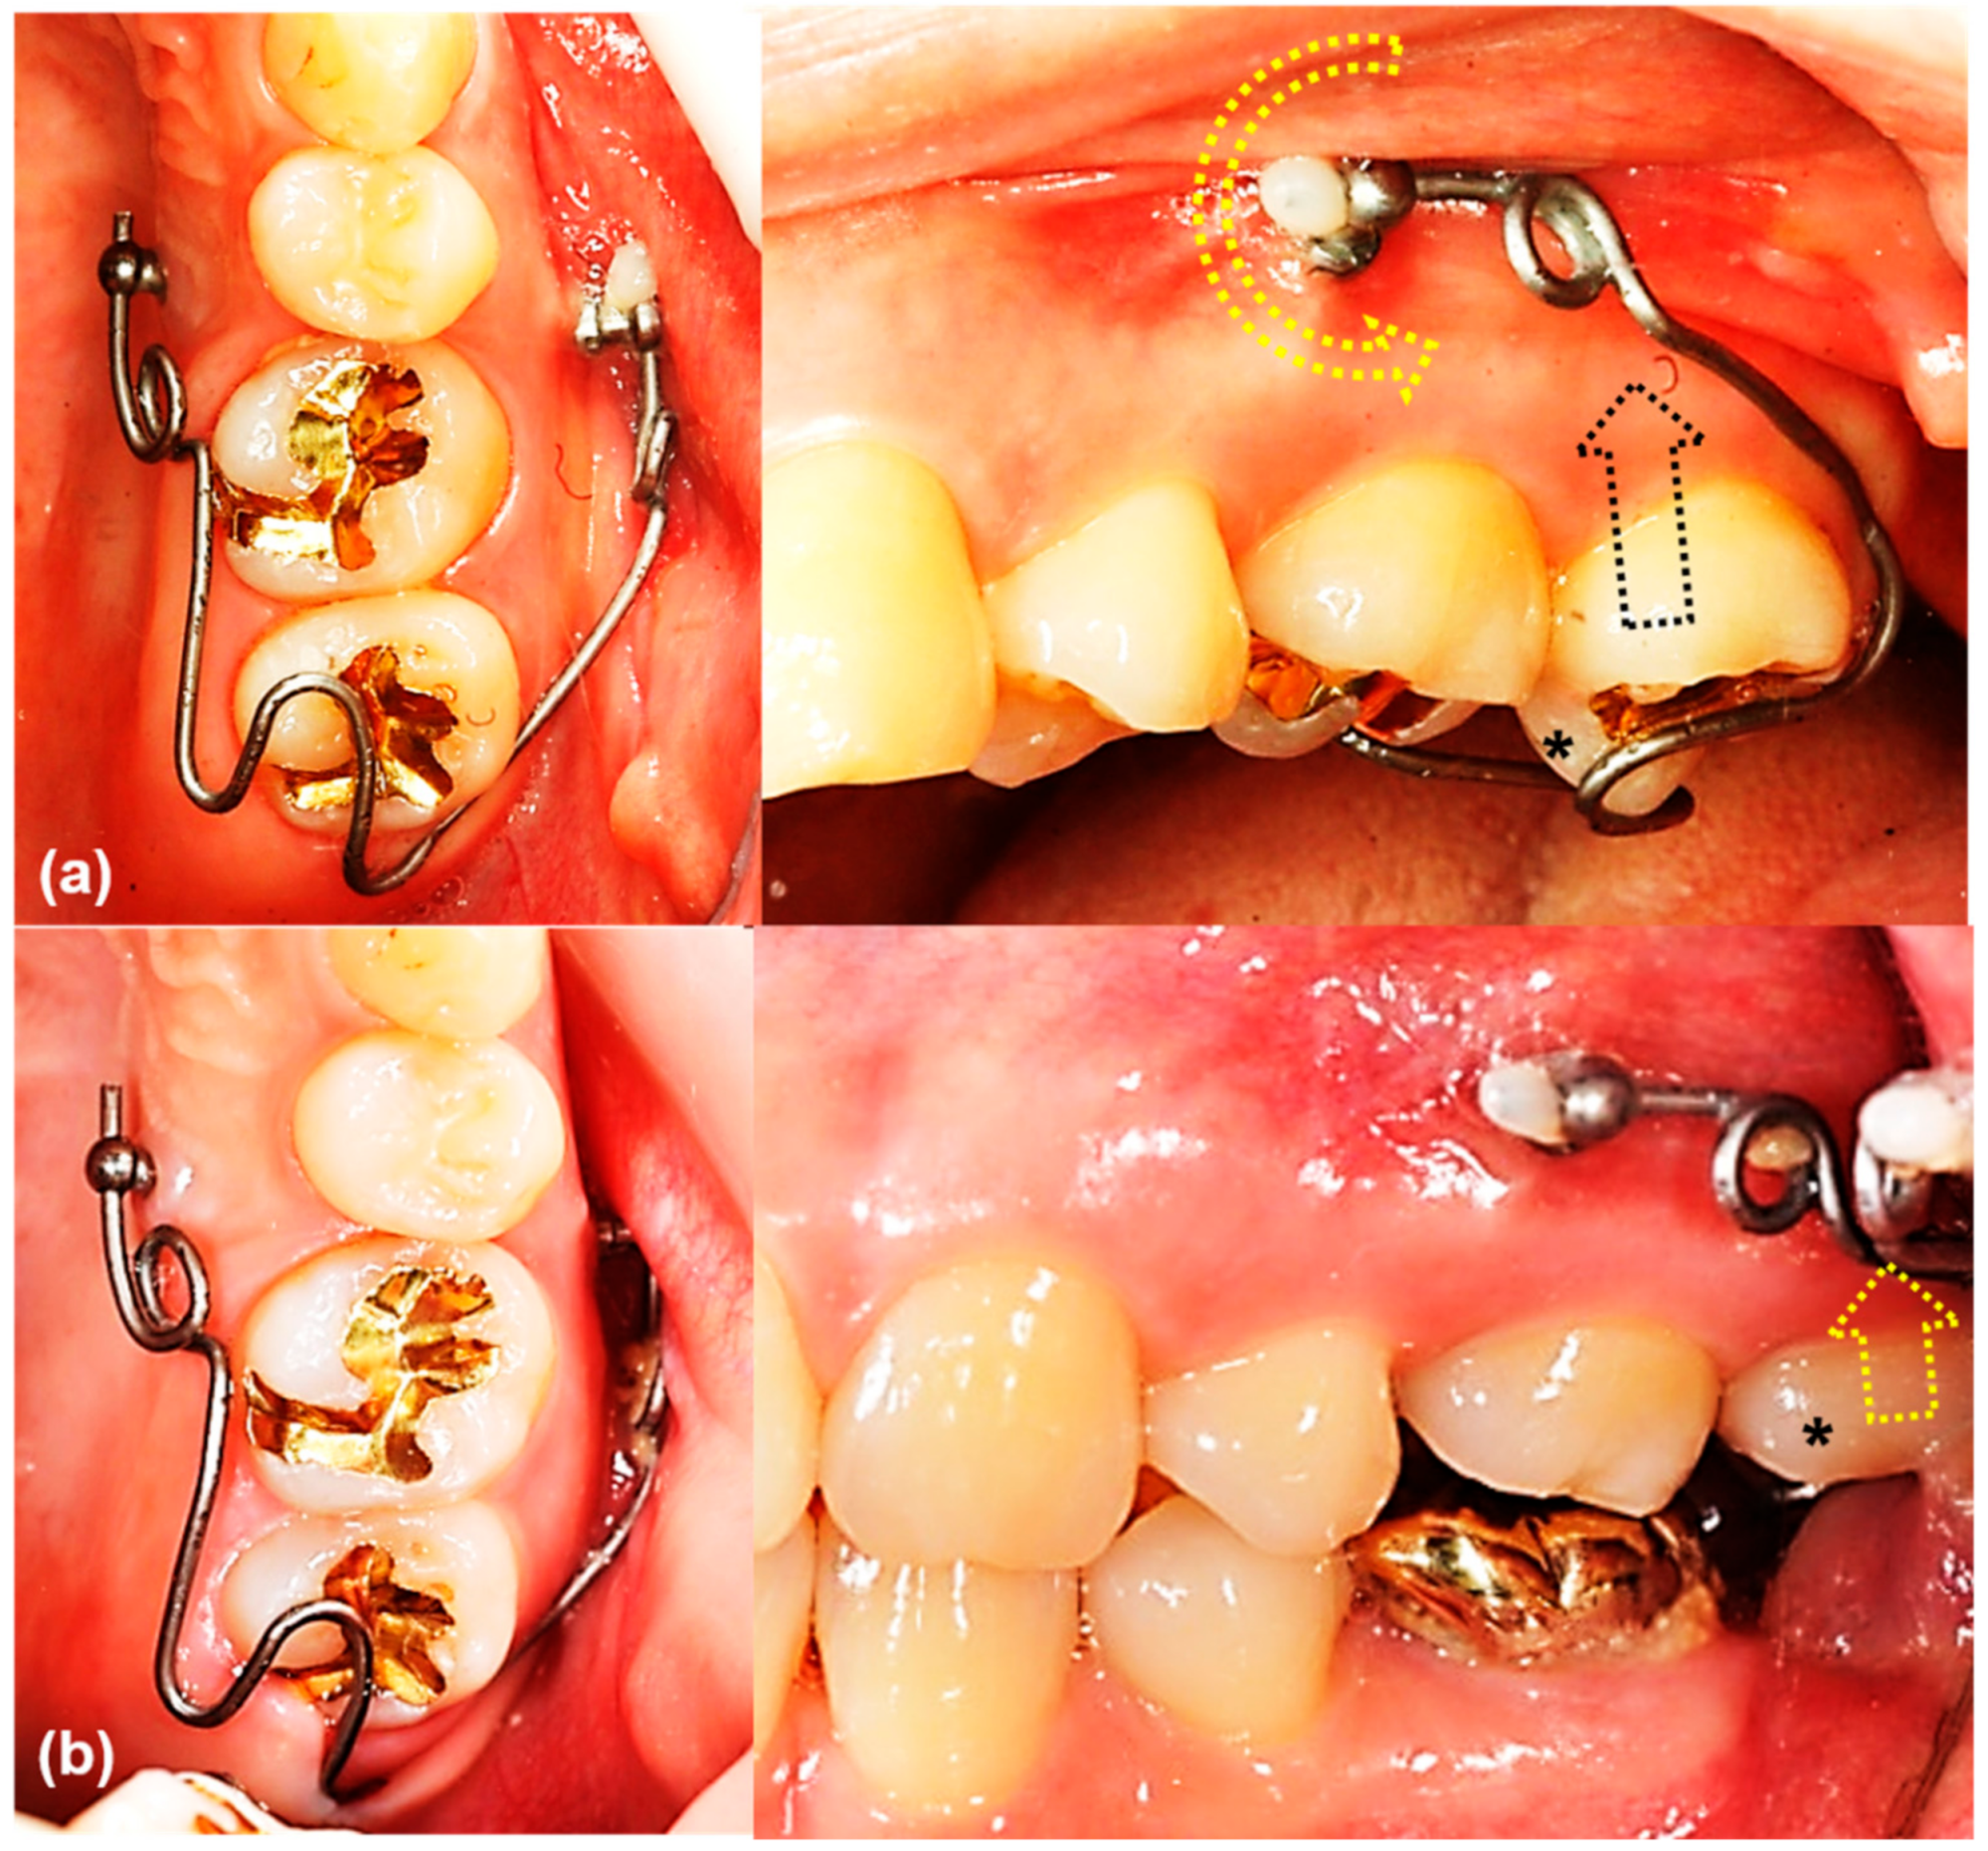

The main result of this study that the rotational resistance of the orthodontic miniscrew with a novel design was increased would be applied to the clinical situation where the increased moment is required. Figure 9 and Figure 10 shows an example of the counterclockwise rotational force applied to an orthodontic miniscrew. A patient with an extruded upper left second molar was treated by one of the authors (K.R.C). The patient agreed and signed an informed consent form that the authors would use photos for the publication of an article. In this case, the orthodontic wire used to intrude the extruded upper left second molar was inserted into a hole in the heads of both orthodontic miniscrews between the upper left second premolar and the upper left first molar on the buccal and palatal side of alveolar bone. On the buccal side, the wire generated a counterclockwise rotational moment on the orthodontic miniscrew. If the amount of moment had been higher than the rotational resistance of the orthodontic miniscrew, the orthodontic miniscrew would have been loosened and the intrusion of the upper left second molar would have failed. In this case, the osseointegration was effective enough to stabilize the orthodontic miniscrew under the heavy moment of the counter-clockwise rotation.

Figure 9.

The orthodontic miniscrew supported the counterclockwise rotational force in a patient with extruded upper left second molar: (a) The patient has an extruded upper left second molar (*), especially the palatal cusp. To intrude this tooth, two orthodontic miniscrews (1.8 mm in diameter, 8.5 mm in length SLA surface treated mini-implant, C-implant, CIMPLANT co., Seoul, Korea) were inserted on the buccal and palatal sides between upper left second premolar and upper left first molar. A spring was designed to apply an intruding force (black dotted arrow) on the palatal cusp of the second molar, with its wire was passing through the holes of the orthodontic miniscrews. The spring generates a counterclockwise rotational moment on the buccal orthodontic miniscrew (yellow dotted arrow); (b) Six months later, the upper left second molar was intruded successfully. Both orthodontic miniscrews stayed stable in spite of the rotational moments.